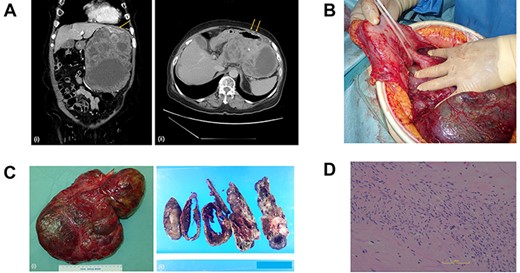

The patient was discharged without complications, deciding against adjuvant chemotherapy despite being informed of the high risk of recurrence. Nine months later, a 2.2 cm mass appeared at the anterior part of the tail of the pancreas, adjacent to the gastric stump (Fig. 2a), and the patient chose chemotherapy in lieu of surgery. We started chemotherapy with low-dose imatinib (200 mg/day) because of the history of febrile neutropenia, subsequently lowering the dose to 100 mg/day due to side effects. She was able to continue the chemotherapy for four years without progression of metastasis.

(A) A computed tomography scan of the abdomen was performed nine months after surgery. (i, coronal view; ii, axial view). A 2.2 cm mass has appeared at the anterior part of the tail of the pancreas (arrow). (B) The postoperative specimen including the recurrent tumor of pancreas from the dorsal side. (C) The tumor is solid without serosal invasion. The specimens on upper line are the pancreas, and those on lower line are the spleen. (D) The tumor cell structure shows more atypism than the original tumor.

Five years after the surgery, the mass had gradually expanded, indicating resistance to imatinib. This time, the patient elected to have surgery rather than the 2nd-line chemotherapy. The mass was attached to the splenic artery and vein, so we performed both distal pancreatectomy and splenectomy. The mass originated from the pancreas, not the stomach, with little adhesion to the gastric stump (Fig. 2b). No other metastatic lesion was observed.

The tumor in the specimen was 3.5 × 3.5 × 2.5 cm in size (Fig. 2c). The morphology and immunohistochemical staining showed features resembling those of the primary gastric GIST, although the tumor cells showed more atypism (Fig. 2d). The final diagnosis was GIST recurrence with a negative surgical margin. Now, six months after the second surgery, she is continuing low-dose imatinib therapy without recurrence.